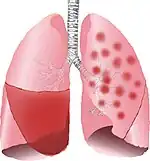

Typical distribution of lobar pneumonia (left in image) and bronchopneumonia (right in image)

It is often contrasted with lobar pneumonia; but, in clinical practice, the types are difficult to apply, as the patterns usually overlap.[2] Bronchopneumonia (lobular) often leads to lobar pneumonia as the infection progresses. The same organism may cause one type of pneumonia in one patient, and another in a different patient.